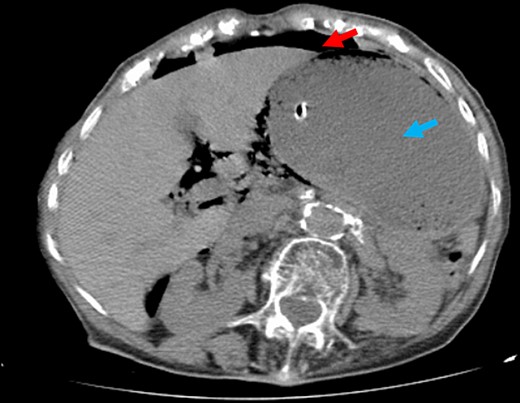

The patient underwent an abdominal plain film, which identified a massive gastric dilation and a pneumoperitoneum was suspected (Fig. 1). In order to confirm these findings, an abdominal computed tomography (CT) was performed, which clearly identified a massive gastric dilation. The stomach reached the pelvis and had an abrupt stricture at the level of the pylorus. A large pneumoperitoneum was also confirmed (Fig. 2).

Abdominal CT. Note the large volume pneumoperitoneum (red arrows) and exuberant gastric dilation (blue arrows).